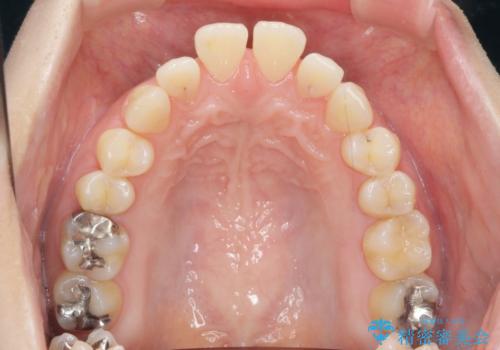

- 出っ歯に見える前歯を治したい、と矯正治療を希望され来院されました。

奥歯の噛み合わせに大きな問題はないので、目立つ前歯の角度・隙間を重点的に整え、審美的な歯並びを獲得できるよう計画します。

治療によりしっかりと前歯の角度が改善され、審美的な歯並びを手に入れることができました。